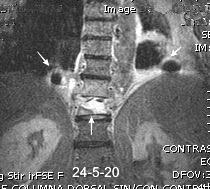

Empiema pleural izquierdo. Absceso del LID. Espondilodiscitis D11-D12.

Potsios C et al. Pyogenic Spondylodiscitis due to Streptococcus constellatus in an Immunocompromised Male Patient: A case Report and Review of the Literature. Case Reports in Infectious Diseases. 2019